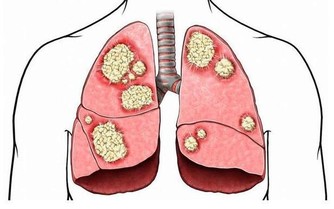

④飲食習慣要改變。平時多吃含植物纖維多的食物,例如蔬菜水果,不僅能預防便秘,還能預防腸癌的發生。同時,每天要多喝水,保證每天攝入2000毫升的水。